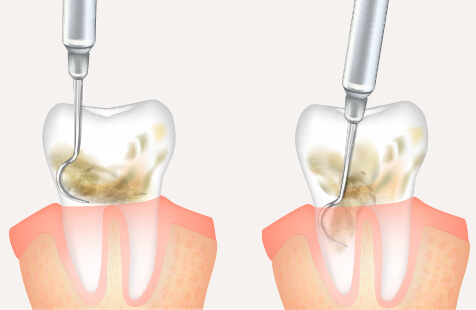

歯の内部から治療する精密根管治療を行っています。

根管治療とは歯の根管の中にある「虫歯に感染した歯の神経」「細菌」「過去に詰めた古い充填材」等を除去していく治療法です。細菌に侵された部分を丁寧に除去・消毒・洗浄を行い、薬液を充填して歯を温存します。

根管の根っこに病巣が発生し、歯根の尖端部分の根尖病巣(歯根嚢胞、歯根肉芽腫)を切除して細菌を取り除きます。根管治療後症状が改善しない場合や根尖病巣が大きく、根管治療で根治できない場合に行います。